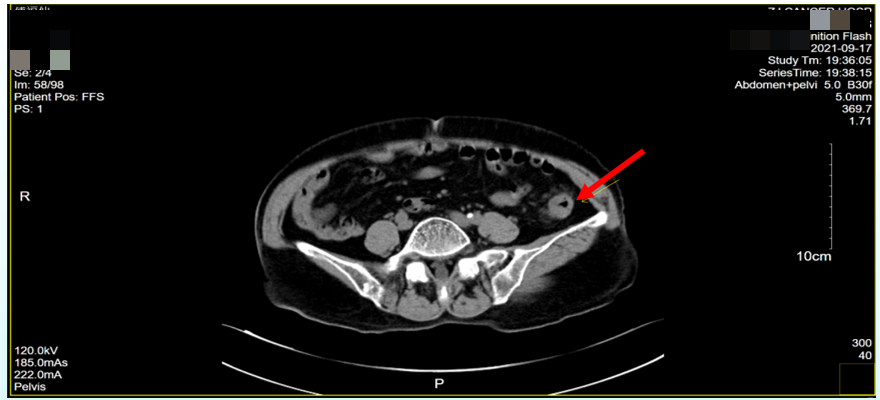

2021年9月17日腹、盆腔CT检查,提示降-乙交界区结肠壁异常增厚,考虑恶性肿瘤,并累及浆膜,肠周淋巴结肿大;直肠壁可疑增厚,结合内镜检查;肝、胰、脾及腹膜后平扫未见明显异常(图2)。